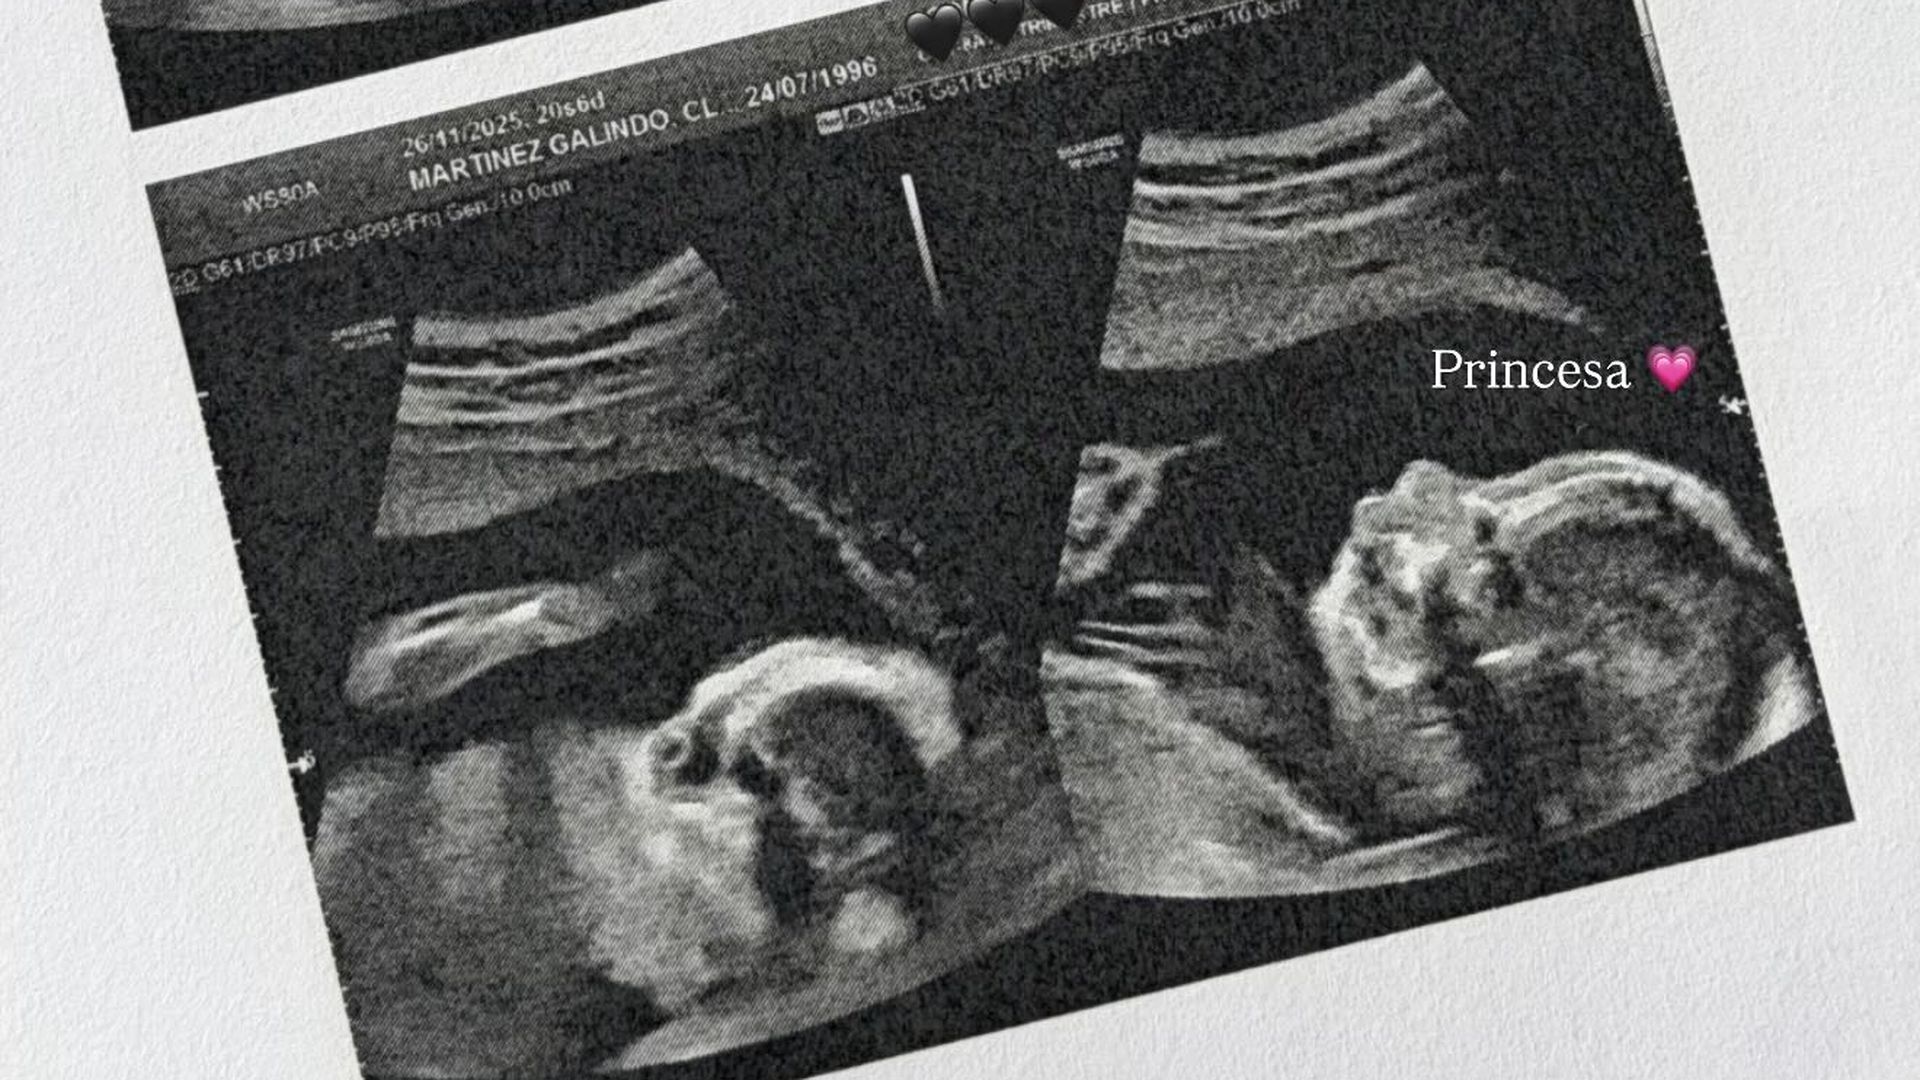

“Tenemos la eco de las 20 semanas que es una de las más importantes. Como todo el mundo me dice que es importante estoy muy nerviosa”, comenzaba diciendo a través de sus ‘stories’. Pronto le empezaron a llegar cientos de mensajes de sus seguidores preguntándole cómo había ido y ella no dudó en contestar. “Chicas todo bien, el doctor me ha recomendado que me haga las pruebas de ADN que ya me hice en su día (y que salieron bien) por un temita”, ha puesto junto a la imagen de la ecografía.

Esta frase ha hecho saltar las alarmas de su comunidad que no han dudado en volver a hablarle para preguntarle sobre “ese temita” por el que tiene que repetir las pruebas de ADN. “Ayer el doctor vio una cosita en la bebé por la que me recomendó hacerme las pruebas de ADN”, ha explicado con sinceridad.

La realidad es que estas pruebas ella se las hizo en otro hospital, por lo que en el que se hizo la ecografía, no consta en su historial médico. “Yo me las realicé porque quise, sin que nadie me las pidiera, simplemente por quedarme tranquila. Así que, cuando le dije que ya las tenía y que había salido todo bien, me dijo que entonces me quedara tranquila, que ya había adelantado el trabajo”, ha continuado diciendo.

Aún así, se las va a hacer de nuevo para quedarse tranquila y descartar cualquier tipo de problema que pueda tener su hija. “Hasta que no hable con mi doctora estaré un poquito inquieta porque así soy. Pero repito: en principio con esos resultados ya queda descartada cualquier anomalía”, ha confesado queriendo ser sincera. Claudia deja claro que desde que visite a su psicóloga compartirá la información con todos sus seguidores para que ellos se queden también tranquilos.